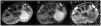

Synovial sarcoma (SS) is a rare malignant neoplasm of the soft tissue adjacent to joints. It is the most commonly diagnosed non-rhabdomyosarcoma soft-tissue sarcoma (STS) in childhood (30%). Its most frequent location is the knee and ankle, and it is the most common STS to affect the foot. Unlike other STS, it has slow growth and an earlier age at diagnosis (adolescents and young adults), which is why many cases are initially misdiagnosed as benign processes. Magnetic resonance imaging (MRI) is key due to its characterisation capabilities as SS shares features with other STS. Definitive diagnosis is achieved through a pathological study that shows the pathognomonic translocation t(x;18)(p11;q11) with the fluorescence in situ hybridisation (FISH) technique. The objective of this article is to highlight the key characteristics that are useful for diagnosing SS, fundamentally through the use of radiological imaging techniques, as well as nuclear medicine and pathological studies, illustrated with cases diagnosed in our centre.

El sarcoma sinovial (SS) es una neoplasia maligna infrecuente del tejido blando adyacente a las articulaciones, siendo el sarcoma de tejidos blandos (STB) de tipo «no rabdomiosarcoma», más diagnosticado en la infancia (30%). Su localización más frecuente es la rodilla y tobillo, representando el STB más común del pie. A diferencia de otros STB, presenta un crecimiento lento y una edad más temprana al diagnóstico (adolescentes y adultos jóvenes), por lo que muchos casos son inicialmente diagnosticados como procesos benignos de forma errónea. La resonancia magnética (RM) es clave para su caracterización, si bien comparte características con otros STB. El diagnóstico definitivo es anatomopatológico, que evidencia la translocación patognomónica t(x;18)(p11;q11) con técnica de hibridación fluorescente in situ (FISH). El objetivo de este artículo, ilustrado con casos diagnosticados en nuestro centro, es resaltar las características claves para el enfoque diagnóstico del SS, fundamentalmente mediante el uso de técnicas de imagen radiológicas, así como estudios de medicina nuclear y anatomopatológicos.